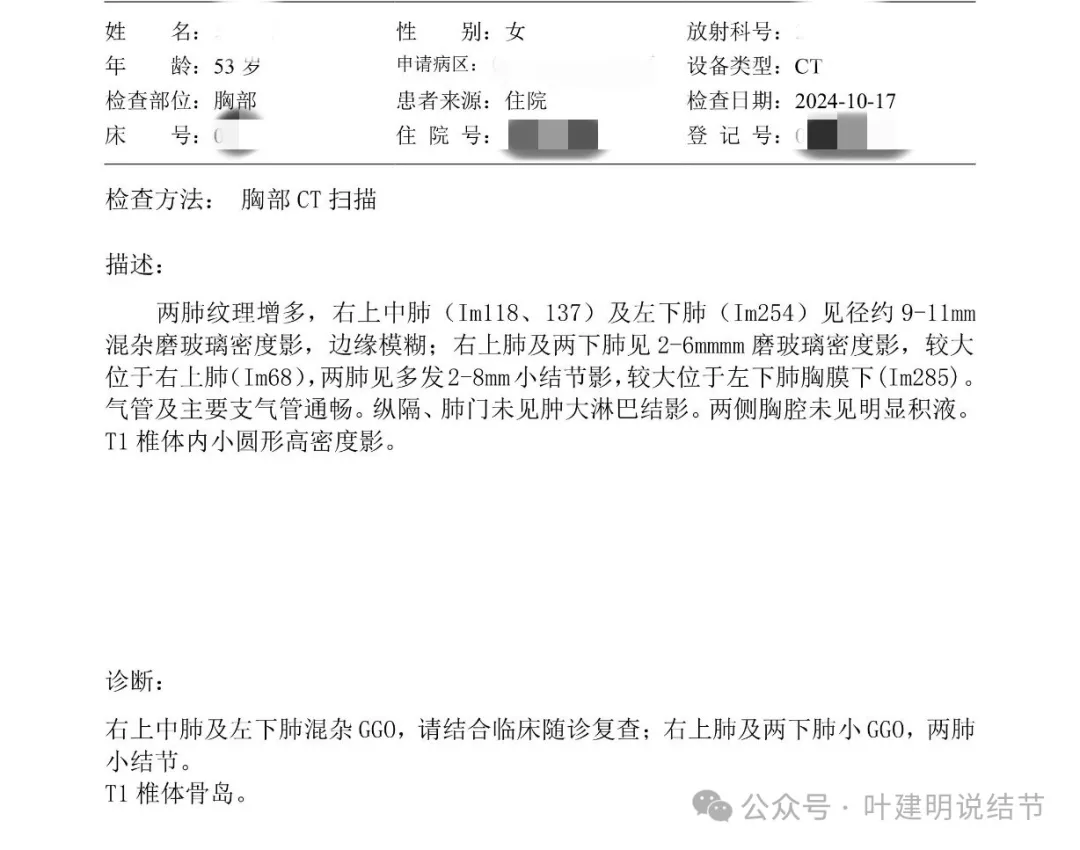

这是10月复查后的报告,多发混杂GGO了。

上海中山医院王群教授意见是考虑炎症可能性大,建议3个月复查。

上海复旦肿瘤医院陈海泉教授诊断是肺诊断性影像异常,建议半年后复查。

上海胸科医院周姓主任坚持两个结节百分之九十恶性,而且在往深处长。

再来看周教授认为4B类的右上后段病灶连续层面影像信息: